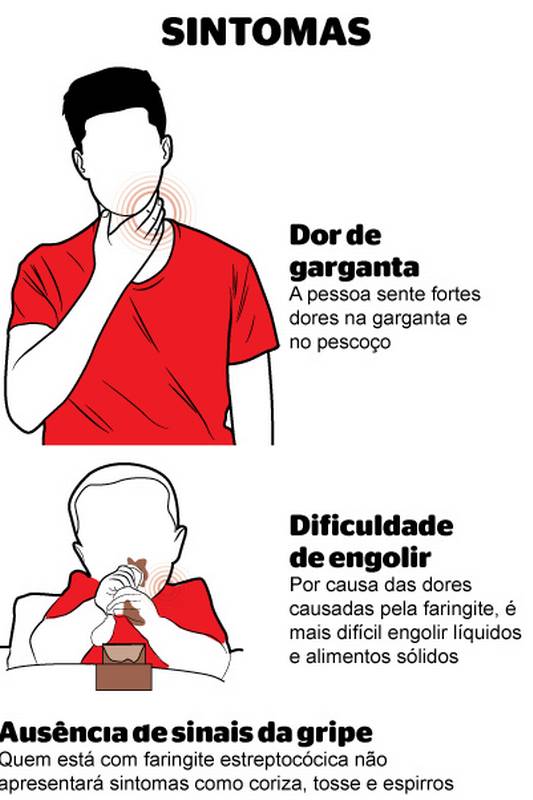

É normal sentir um leve desconforto, mas alguns sinais na sua garganta indicam que é hora de procurar um médico. Dor que não passa em uma semana, febre alta persistente ou dificuldade séria para engolir são sinais claros. Pus nas amígdalas ou irritação que dura mais de 15 dias também não devem ser ignorados. Fatores como fumar ou viver em locais poluídos podem agravar a situação e manter a garganta irritada por muito tempo.

| Sintomas de Alerta | Febre alta persistente, dificuldade severa para engolir, pus nas amígdalas, dor que não melhora em uma semana. |

Sinais de Alerta: Quando Procurar um Médico

É fundamental saber identificar quando a dor de garganta deixa de ser um incômodo comum e se torna algo que exige atenção médica. Procure ajuda profissional se você apresentar sinais de alerta na dor de garganta. Isso inclui dificuldade severa para engolir, febre alta que não cede, surgimento de pus nas amígdalas ou se a dor persistir por mais de uma semana.

Dor de garganta com febre e pus, o que pode ser?

Quando há febre alta e pus visível nas amígdalas, pode ser um sinal de infecção bacteriana, como a amigdalite estreptocócica. É importante procurar um médico para diagnóstico e tratamento adequados, pois pode ser necessário o uso de antibióticos. Fica tranquila, o especialista vai te orientar.